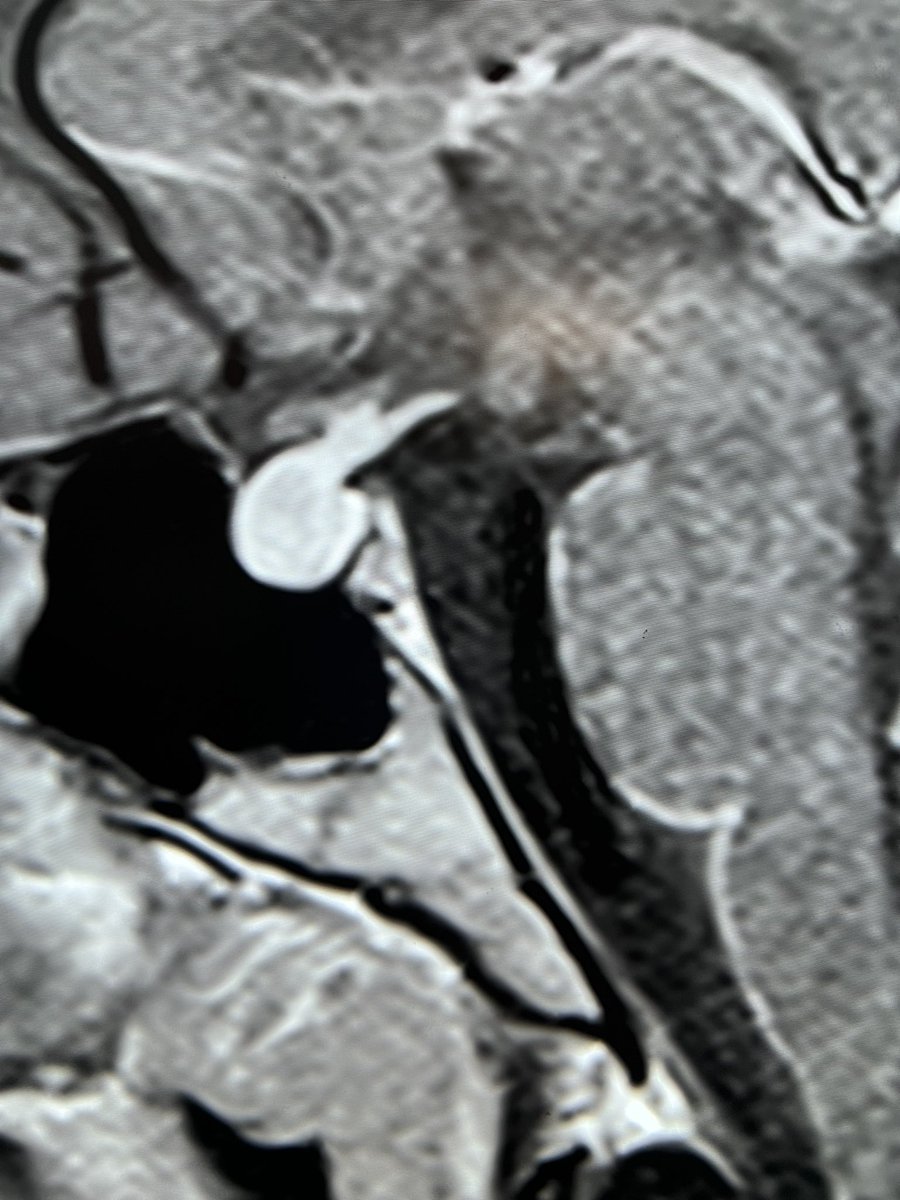

Tip of the day 💡: The pituitary and it’s stalk can enlarge and enhance like this during puberty. Physiology is a range of normality.